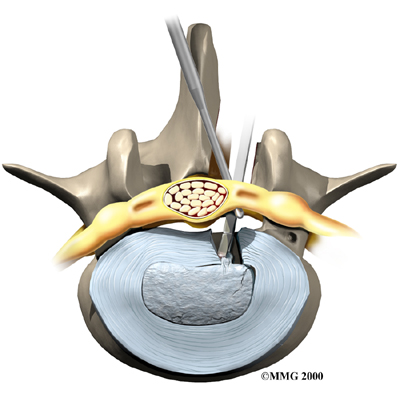

Some patients who continue to have symptoms are given an (ESI). Steroids are powerful anti-inflammatories. In an ESI, medication is injected into the space around the lumbar spinal nerves where they branch off of the spinal cord. This area is called the epidural space. Some doctors inject only a steroid. Most doctors, however, combine a steroid with a long-lasting numbing medication. Generally, an ESI is given only when other treatments aren't working. But ESIs are not always successful in relieving pain. If they do work, they often provide only temporary relief.